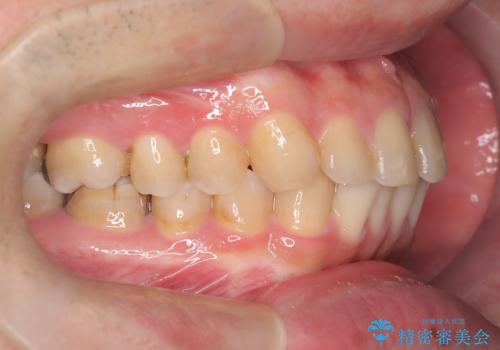

正中離開・クロスバイト・すきっ歯・叢生|インビザラインで治療

- 前歯の隙間と歯のデコボコを主訴にご来院された患者様です。

加えて、上下の奥歯が全く咬み合わないシザーズバイトの状態も認められました。

矯正検査の結果、非抜歯でインビザラインによる治療が可能と判断し、治療を行いました。

歯の隙間とデコボコ、シザーズバイトも改善され、咬み合わせや見た目が整い、患者様にも大変ご満足いただけました。